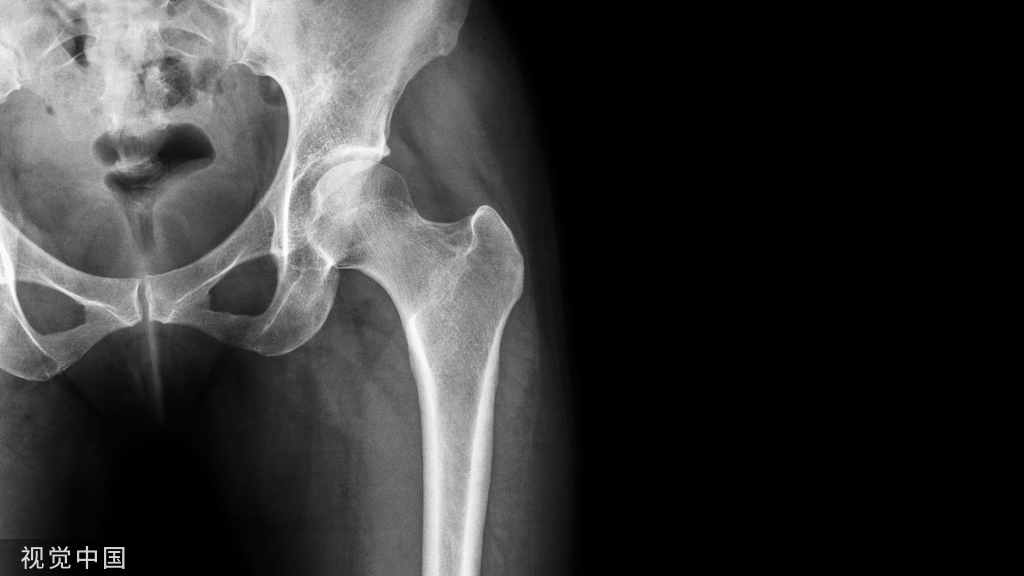

☆特异性腰痛(Specific low back pain):与疾病、感染、损伤、创伤或结构畸形有关的疼痛。诊断与疼痛之间可能存在因果关系。比如我们最常见的腰椎间盘突出症、腰椎管狭窄症、脊柱结核、脊柱感染、脊柱肿瘤、脊柱骨折等等。今天我们暂时不去过多解读。

☆非特异性腰痛(Nonspecific low back pain NLBP)一种无法确定特定病因或结构以解释患者所感知到的疼痛。这一类患者占腰痛85%左右